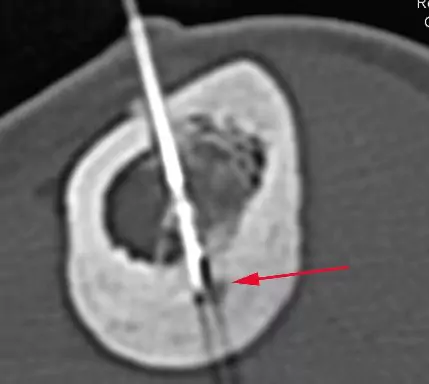

Preparation: You'll be administered local and general anesthesia, ensuring your comfort throughout the procedure. Imaging Guidance: Using CT scans, the physician locates the tumor with pinpoint accuracy. Insertion of the Electrode: A thin electrode is guided to the tumor site without an incision. Radiofrequency Energy Application: The electrode emits radiofrequency energy, generating heat that destroys the tumor. Monitoring: Throughout the procedure, the physician monitors the temperature to ensure optimal tumor destruction. Closing Incision: Once the procedure is complete, the incision is closed with sutures or adhesive strips.